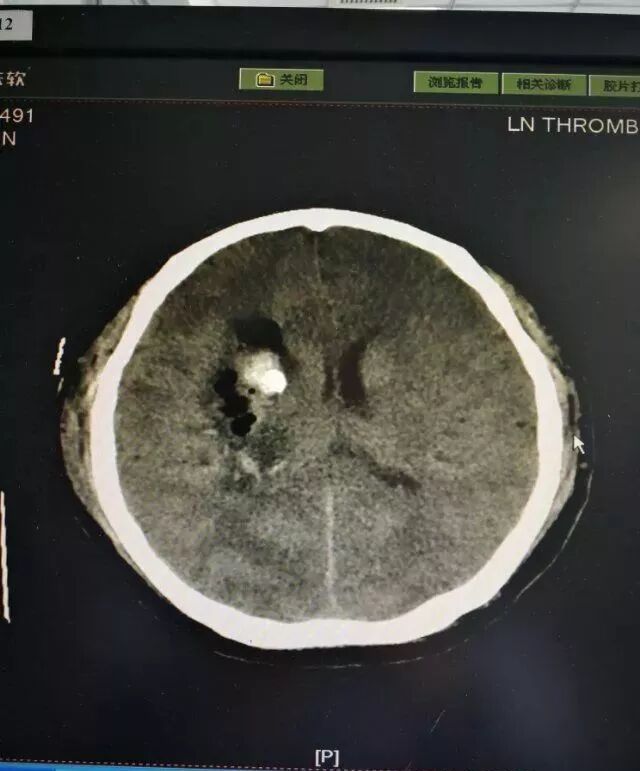

患者男性,53岁,以右侧基底节出血为诊断入院,量约50毫升。

术前片子

术后第一天复查,患者清醒,言语正常。